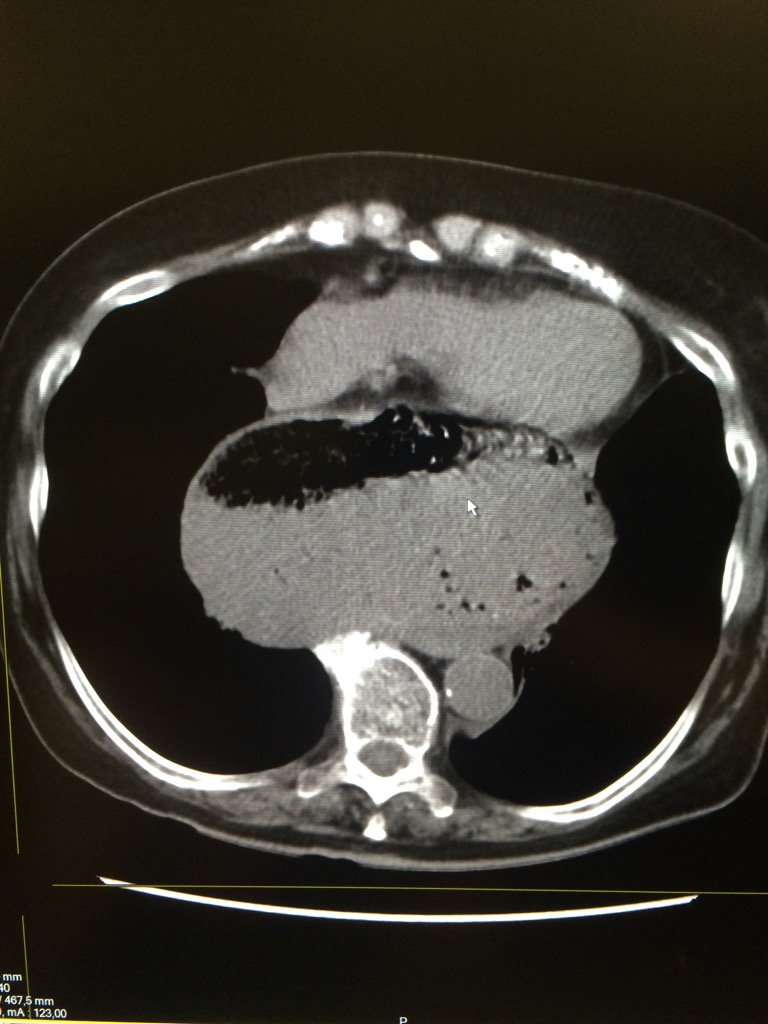

Posterior mediastinal mass #FRCPCAnes

Obstructive shock / compressed heart !!caused by gastric volvulus at level of para-oesophagal hernia (intrathoracic)

EGLS_'s tweet image. Obstructive shock / compressed heart !!caused by gastric volvulus at level of para-oesophagal hernia (intrathoracic)